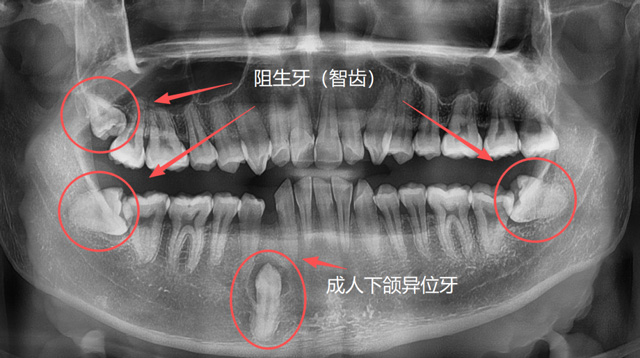

刘伟博士:解剖位置、解剖结构异常的牙齿,拔牙难度更大一些。包括位置异常的阻生牙、异位牙,结构异常的如牙根弯曲、牙根多的牙,还有因为长期慢性炎症造成牙周粘连的牙,以及一些完全退缩到骨头里面的残根,都有一定的难度。

成人异位牙、阻生牙(智齿)

有些人因为牙列拥挤、乳牙滞留或先天发育等原因,恒牙没有在正常的位置萌出,反而往上颌窦、鼻腔等方向生长;称为“异位牙”,还有的牙因为全部或部分埋在了牙槽骨里,无法萌出,称为“阻生牙”,很多智齿就是这样的情况;还有一些超出正常数量的“多生牙”,通常也埋在牙槽骨里无法萌出。